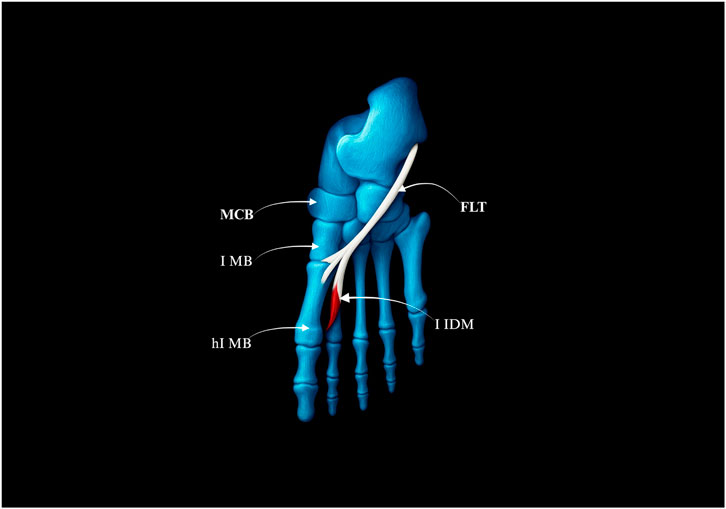

Figure 4. Type I of the fibularis longus tendon. (a) Type Ia of the fibularis longus tendon. (b) Type Ib of the fibularis longus tendon. MCB–medial cuneiforme bnone. I MB–first metatarsal bone hI MB–head of the first metatarsal bone. FLT–fibularis longus tendon.

Type I–Single Distal Attachment (71.3% of cases; 67/94).

• Subtype Ia: Tendon inserts into the lateral tubercle of the base of the first metatarsal bone (49 cases) – Fig, 4a.

• Subtype Ib: Tendon inserts into the head of the first metatarsal bone (18 cases) – Figure 4b.

Type II–Bifurcated Distal Attachment (24.5% of cases; 23/94).

• Subtype IIa: Main tendon inserts into the lateral tubercle of the base of the first metatarsal bone; accessory band inserts into the medial cuneiform (17 cases) – Figure 5a.

• Subtype IIb: Strong accessory band inserts into the base of the first metatarsal and medial cuneiform bones, and additional slips attach to the fourth interosseus dorsalis muscle (4 cases) – Figure 5b.

• Subtype IIc: Accessory band inserts into the first interosseus dorsalis muscle (2 cases) – Figure 5c.

Figure 5. Type II of the fibularis longus tendon. (a) Type IIa of the fibularis longus tendon. (b) Type IIb of the fibularis longus tendon. (c) Type IIc of the fibularis longus tendon. FLT–fibulars longus tendon. MCB–medial cuneiforme bone. I MB–first metatarsal bone. hI MB–head of the first metatarssal bone. IV IDM - fourth interosseus dorsalis muscle. I IDM–first interosseus dorsalis muscle.